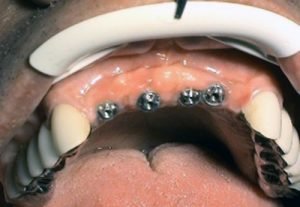

Prosthetic treatment in a toothless jawbone carried - 5 implants

1. PHASE - implant placement

2. PHASE - state before the provisional solution was made

3. PHASE - making a temporary solution

4.PHASE - implant placement